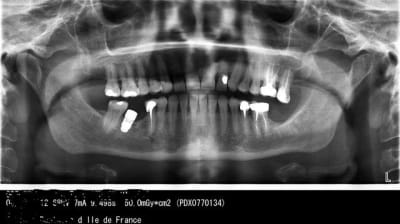

cette patiente a de petites douleurs au niveau de 45-46

l'implant n'est pas posé en situation idéal .. certes

le niveau osseux a changé entre les 2 panos

Plus sérieusement, il me semble qu'un bridge implanto-dentoporté ait été fait (je suis sur mon téléphone, ce n'est pas très net...).

bref, pour revenir à la question, je dirais: la 7 en souffrance parla proximité du clou. difficile d'ameliorer la situation avec l'implant

Distance implant-dent : 1,5 mm mini

Sans doute implant trop gros par rapport à l'os dispo, non ?